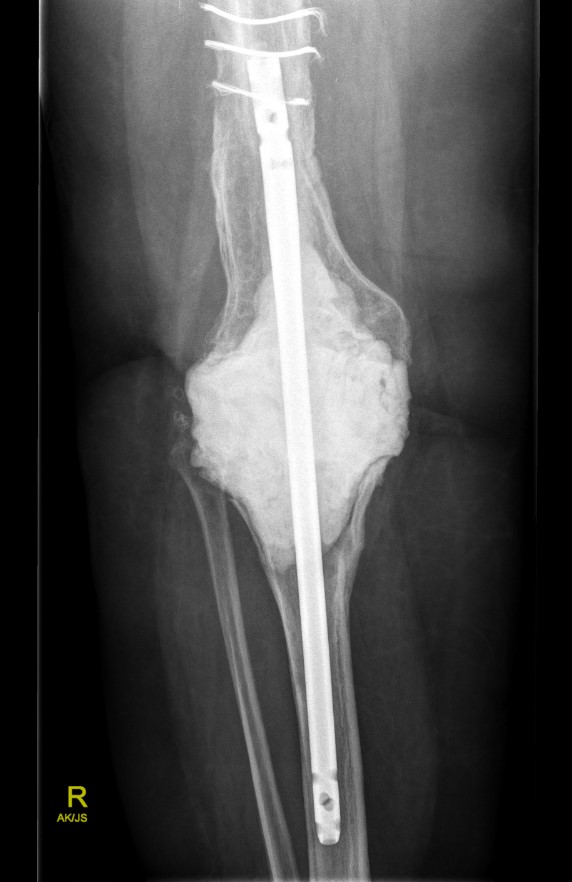

A. Bridging nail

Bridging nail

Modular nail